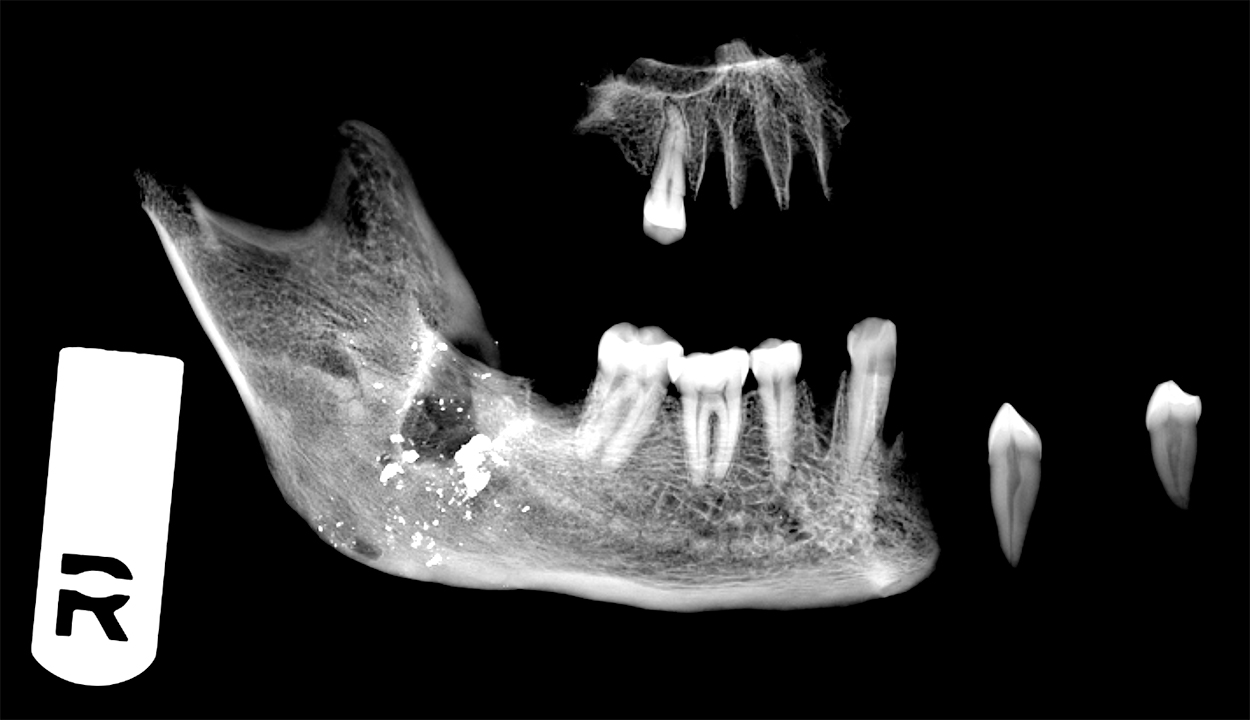

X-ray photo of from bones associated with the Sugar Land 95 projectExhaustive laboratory analysis and archival research went into the compilation of a 500-page report of findings revealing the cemetery was connected to Bullhead Convict Labor Camp, a camp that operated there from circa 1875 to 1908. Reign Clark returned there to oversee the reinterment process of the “Sugar Land 95” in November 2019, where they now rest in their original graves.

This presentation will discuss the excavation of the remains, archeothanatology, and bioarcheological interpretations of the “Sugar Land 95.” Analysis revealed atypical mortuary practices, disease, malnutrition, and trauma endured, among other health insults, by the prisoners of the convict labor camp. DNA and isotope analysis as well as genealogical research continues today in the quest for locating descendants and to put names on markers at the Bullhead Convict Labor Camp Cemetery.